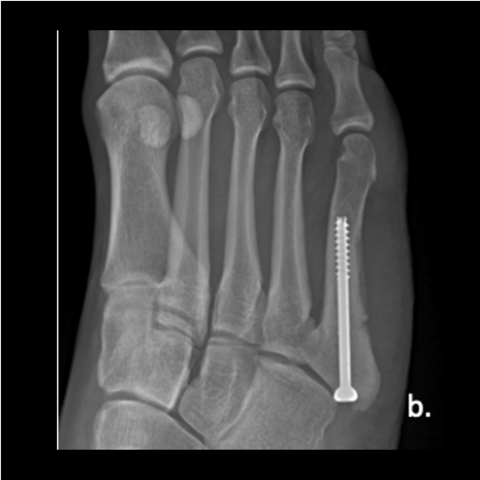

Figure 1b

Figure 1b. A 23-year-old male trainee twisted his foot while running, presenting a week or 2 later. Here is an injury film.